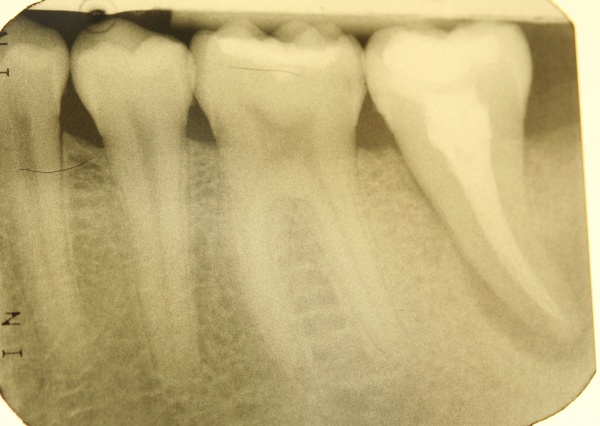

Diagnostische Parameter für die Beurteilung der dentalen und der periimplantären Zustände sind die Plaqueakkumulation, die Sondierungstiefen des Zahnes und des Implantates, Bluten auf Sondierung, Suppuration und der radiographische Knochenverlust (Salvi & Lang 2004). Unabdingbar ist im Minimum eine Sechspunktmessung (Sondiertiefen und klinischer Attachmentlevel). Immer wieder hört man von der Befürchtung, dass durch ein Sondieren des Implantates dieses geschädigt wird. In einer histomorphometrischen Studie an Hunden haben Etter et al. (2002) die Heilung des periimplantären Weichgewebes nach standardisiert klinischem Sondieren untersucht. Die Heilung des Epithelansatzes nach Sondierung des gesunden periimplantären Gewebes ist nach fünf Tagen abgeschlossen. Erfahrungsgemäß ist bei besonders aufmerksamem und vorsichtigem Sondieren ein äußerst geringes Verletzungsrisiko gegeben. Auch diese Techniken können in einem Praktikum bei einem Parodontologen aufgefrischt werden.

Im Rahmen einer solchen Nachuntersuchung werden neben der Plaqueakkumulation die klinischen Parameter Sondiertiefe und klinischer Attachmentlevel (6-fach je Zahn / Implantat), Bluten nach Sondieren (BnS), Suppuration und gegebenenfalls der radiographische Knochenverlust (Salvi & Lang 2004) erfasst.